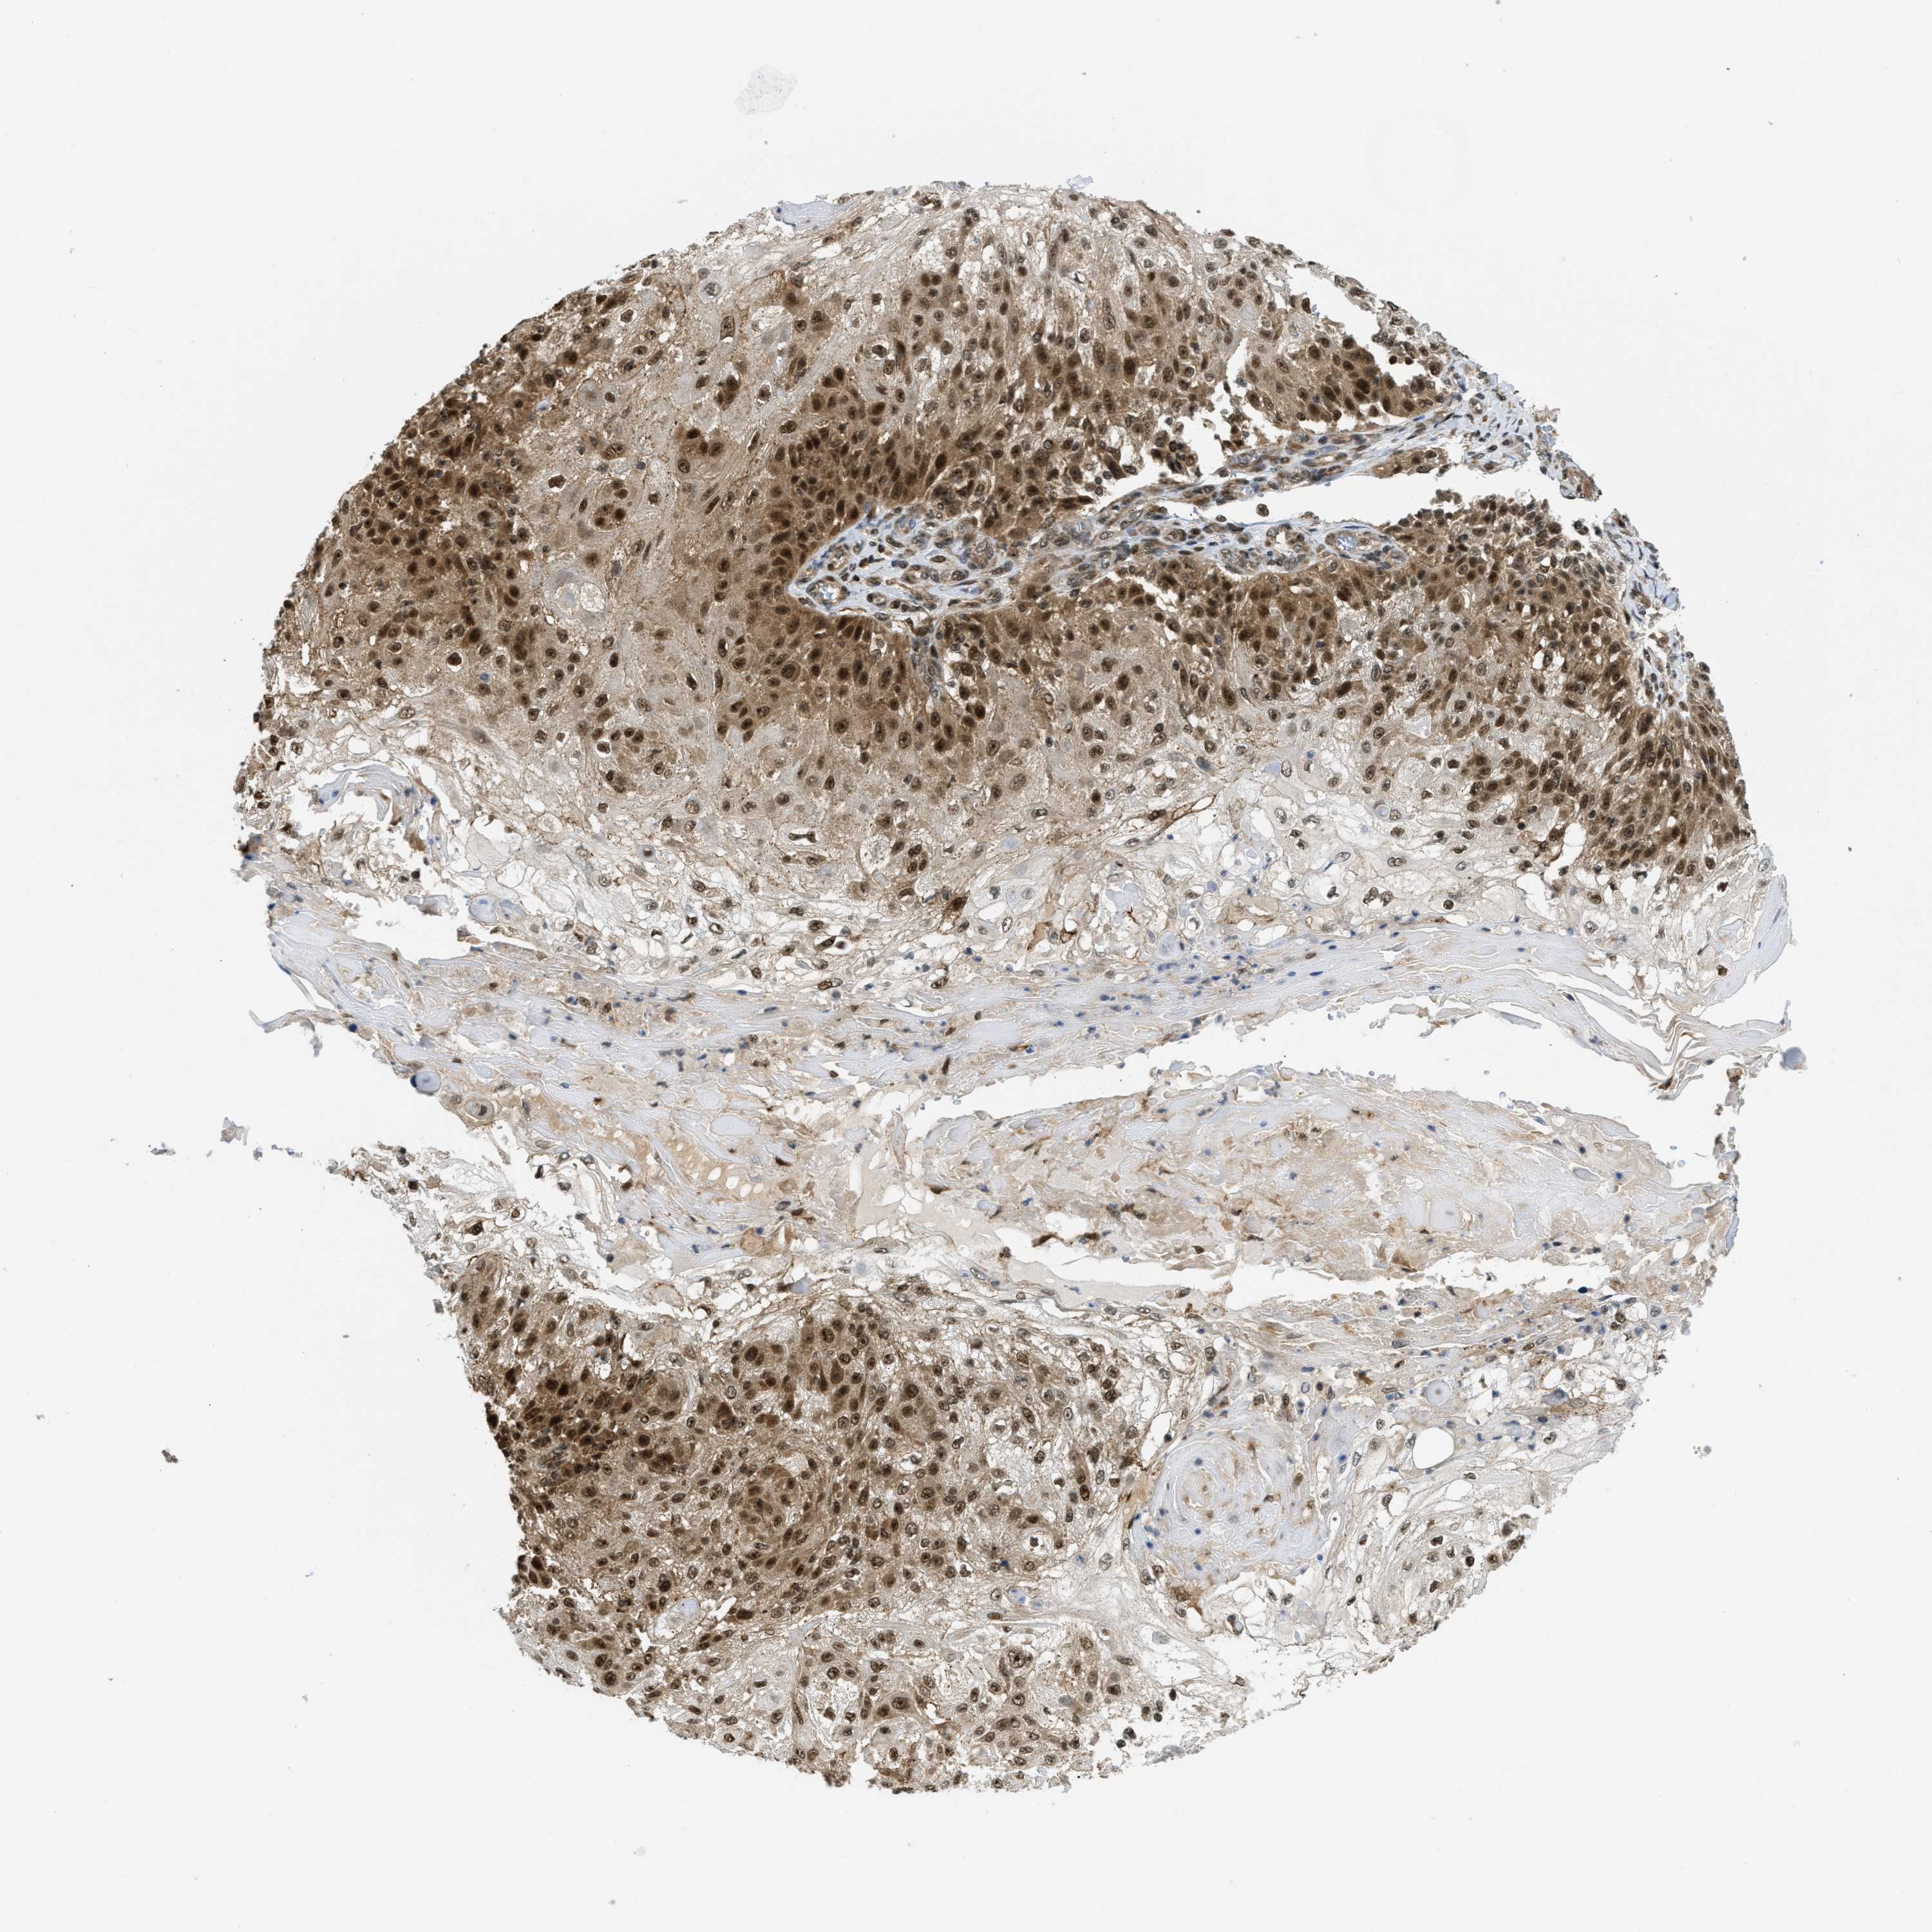

SKIN CANCER - Protein expressioni

A mouse-over function shows sample information and annotation data. Click on an image to view it in a full screen mode. Samples can be filtered based on level of antibody staining by selecting one or several of the following categories: high, medium, low and not detected. The assay and annotation is described here.

Each image is clickable and will lead to virtual microscopy that enables deeper exploration of all samples and also displays staining intensity scores, fraction scores and subcellular localization as well as patient and tissue information for each sample.

Antibody HPA024702

Antibody CAB017041

Staining

High

Medium

Low

Not detected

Intensity

Strong

Moderate

Weak

Negative

Quantity

>75%

75%-25%

<25%

None

Location

Nuclear

Cytoplasmic/membranous

Cytoplasmic/membranous,nuclear

Basal cell carcinoma

Squamous cell carcinoma, NOS

Squamous cell carcinoma, metastatic, NOS